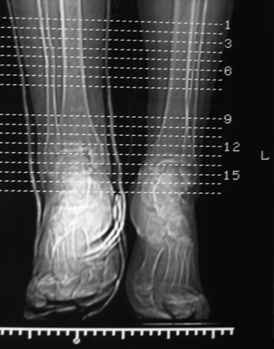

Посмотрели снимки после репозиции - не понравилась зона синдесмоза.

Сделали 3/4-е - впечатление, что в 99-том там что-то было. На

5.11.09г. запланирована КТ.